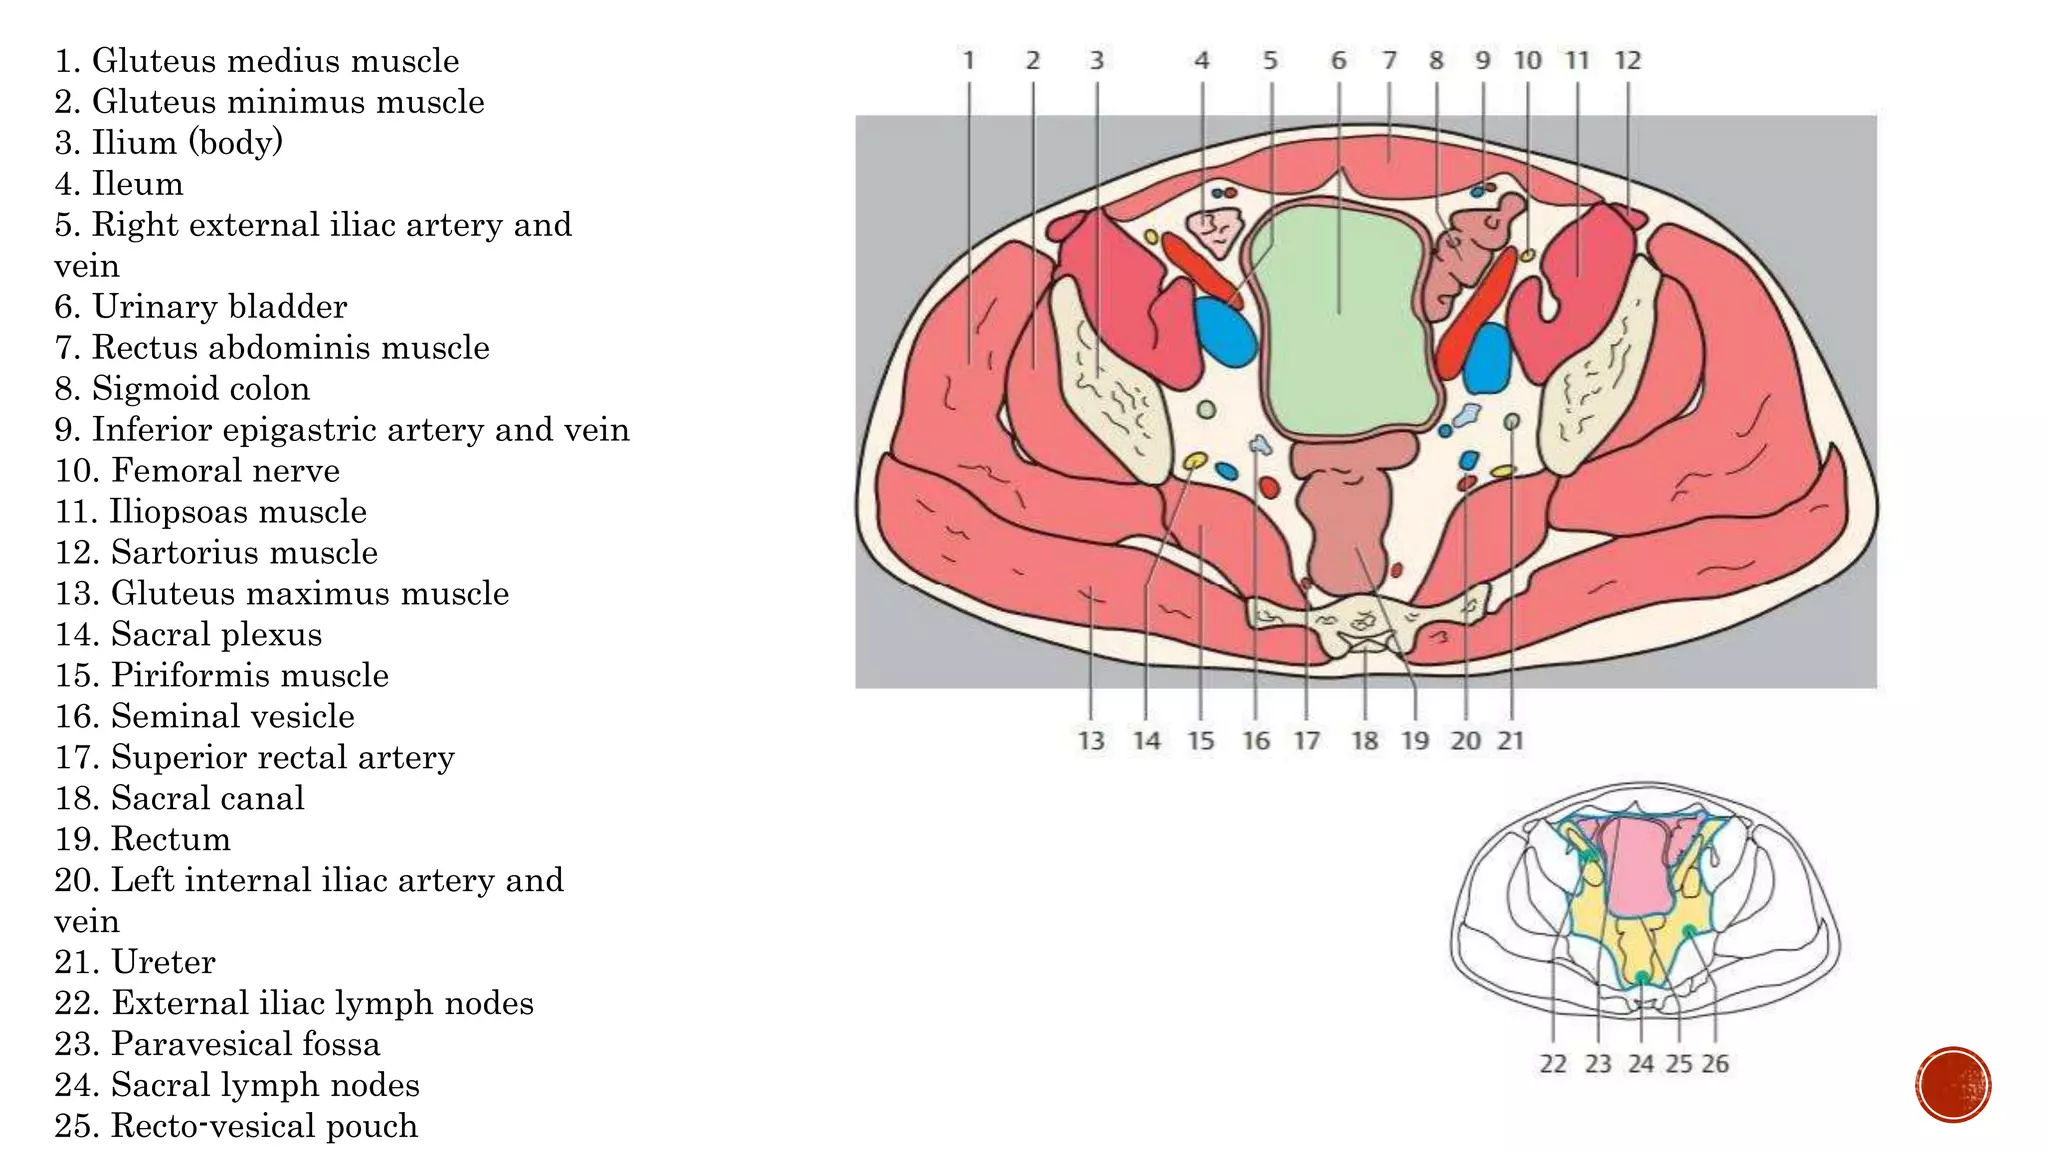

The document describes the anatomy of the abdomen and pelvis region of the human body. It lists over 40 structures and their locations, including major organs like the liver, kidneys, intestines, blood vessels and muscles of the abdominal wall and pelvis. The structures are grouped into sections focusing on different anatomical areas like the abdomen, retroperitoneum, pelvis and gluteal region.